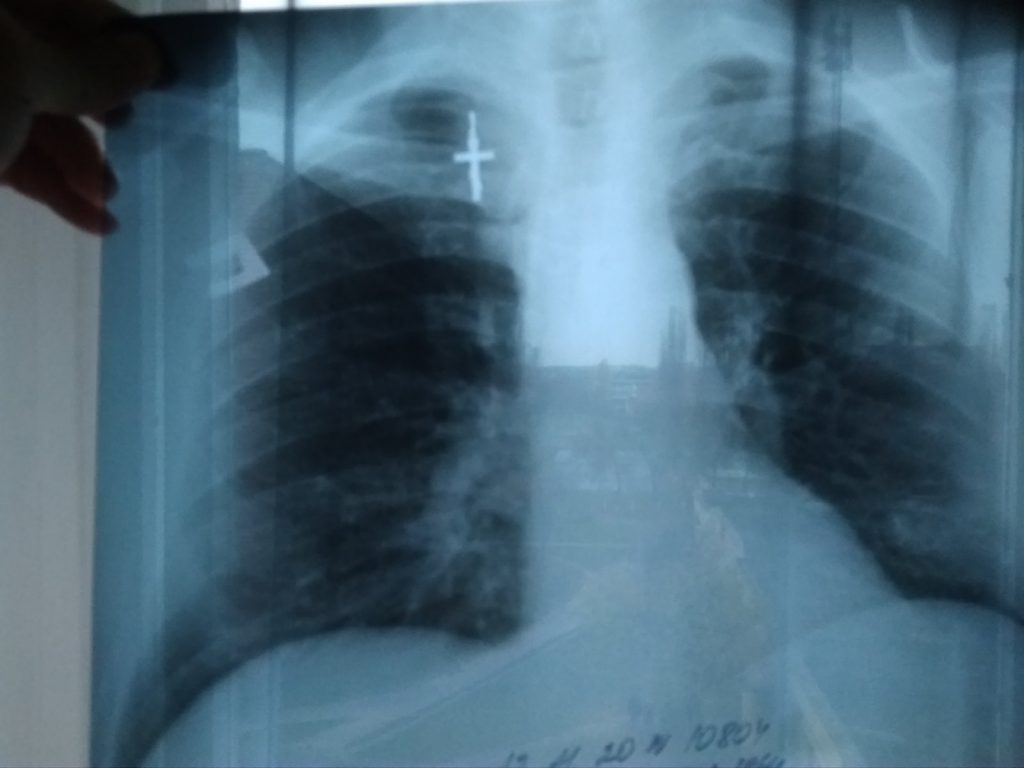

Врач также дала направление в 202 кабинет на снимок легких.

Совет 2: Чтобы быстро пройти рентген приходите в 202-й кабинет заранее, до 8:00, иначе попадете в очередь. Мой приятель ждал результата полдня, мне удалось получить заключение за 1,5 часа.